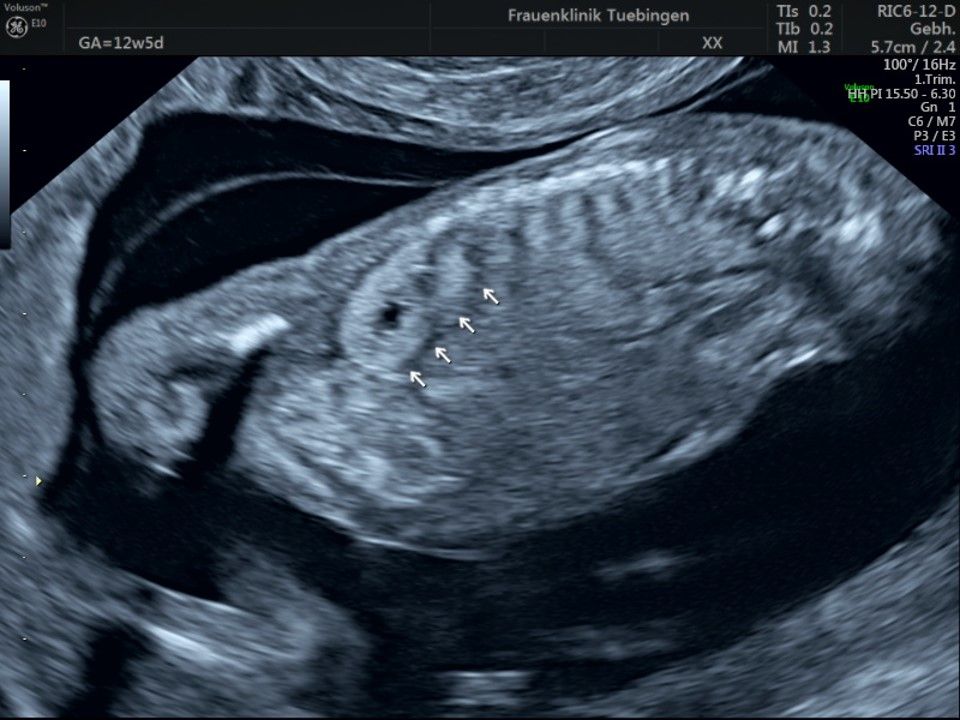

Bauchwanddefekt